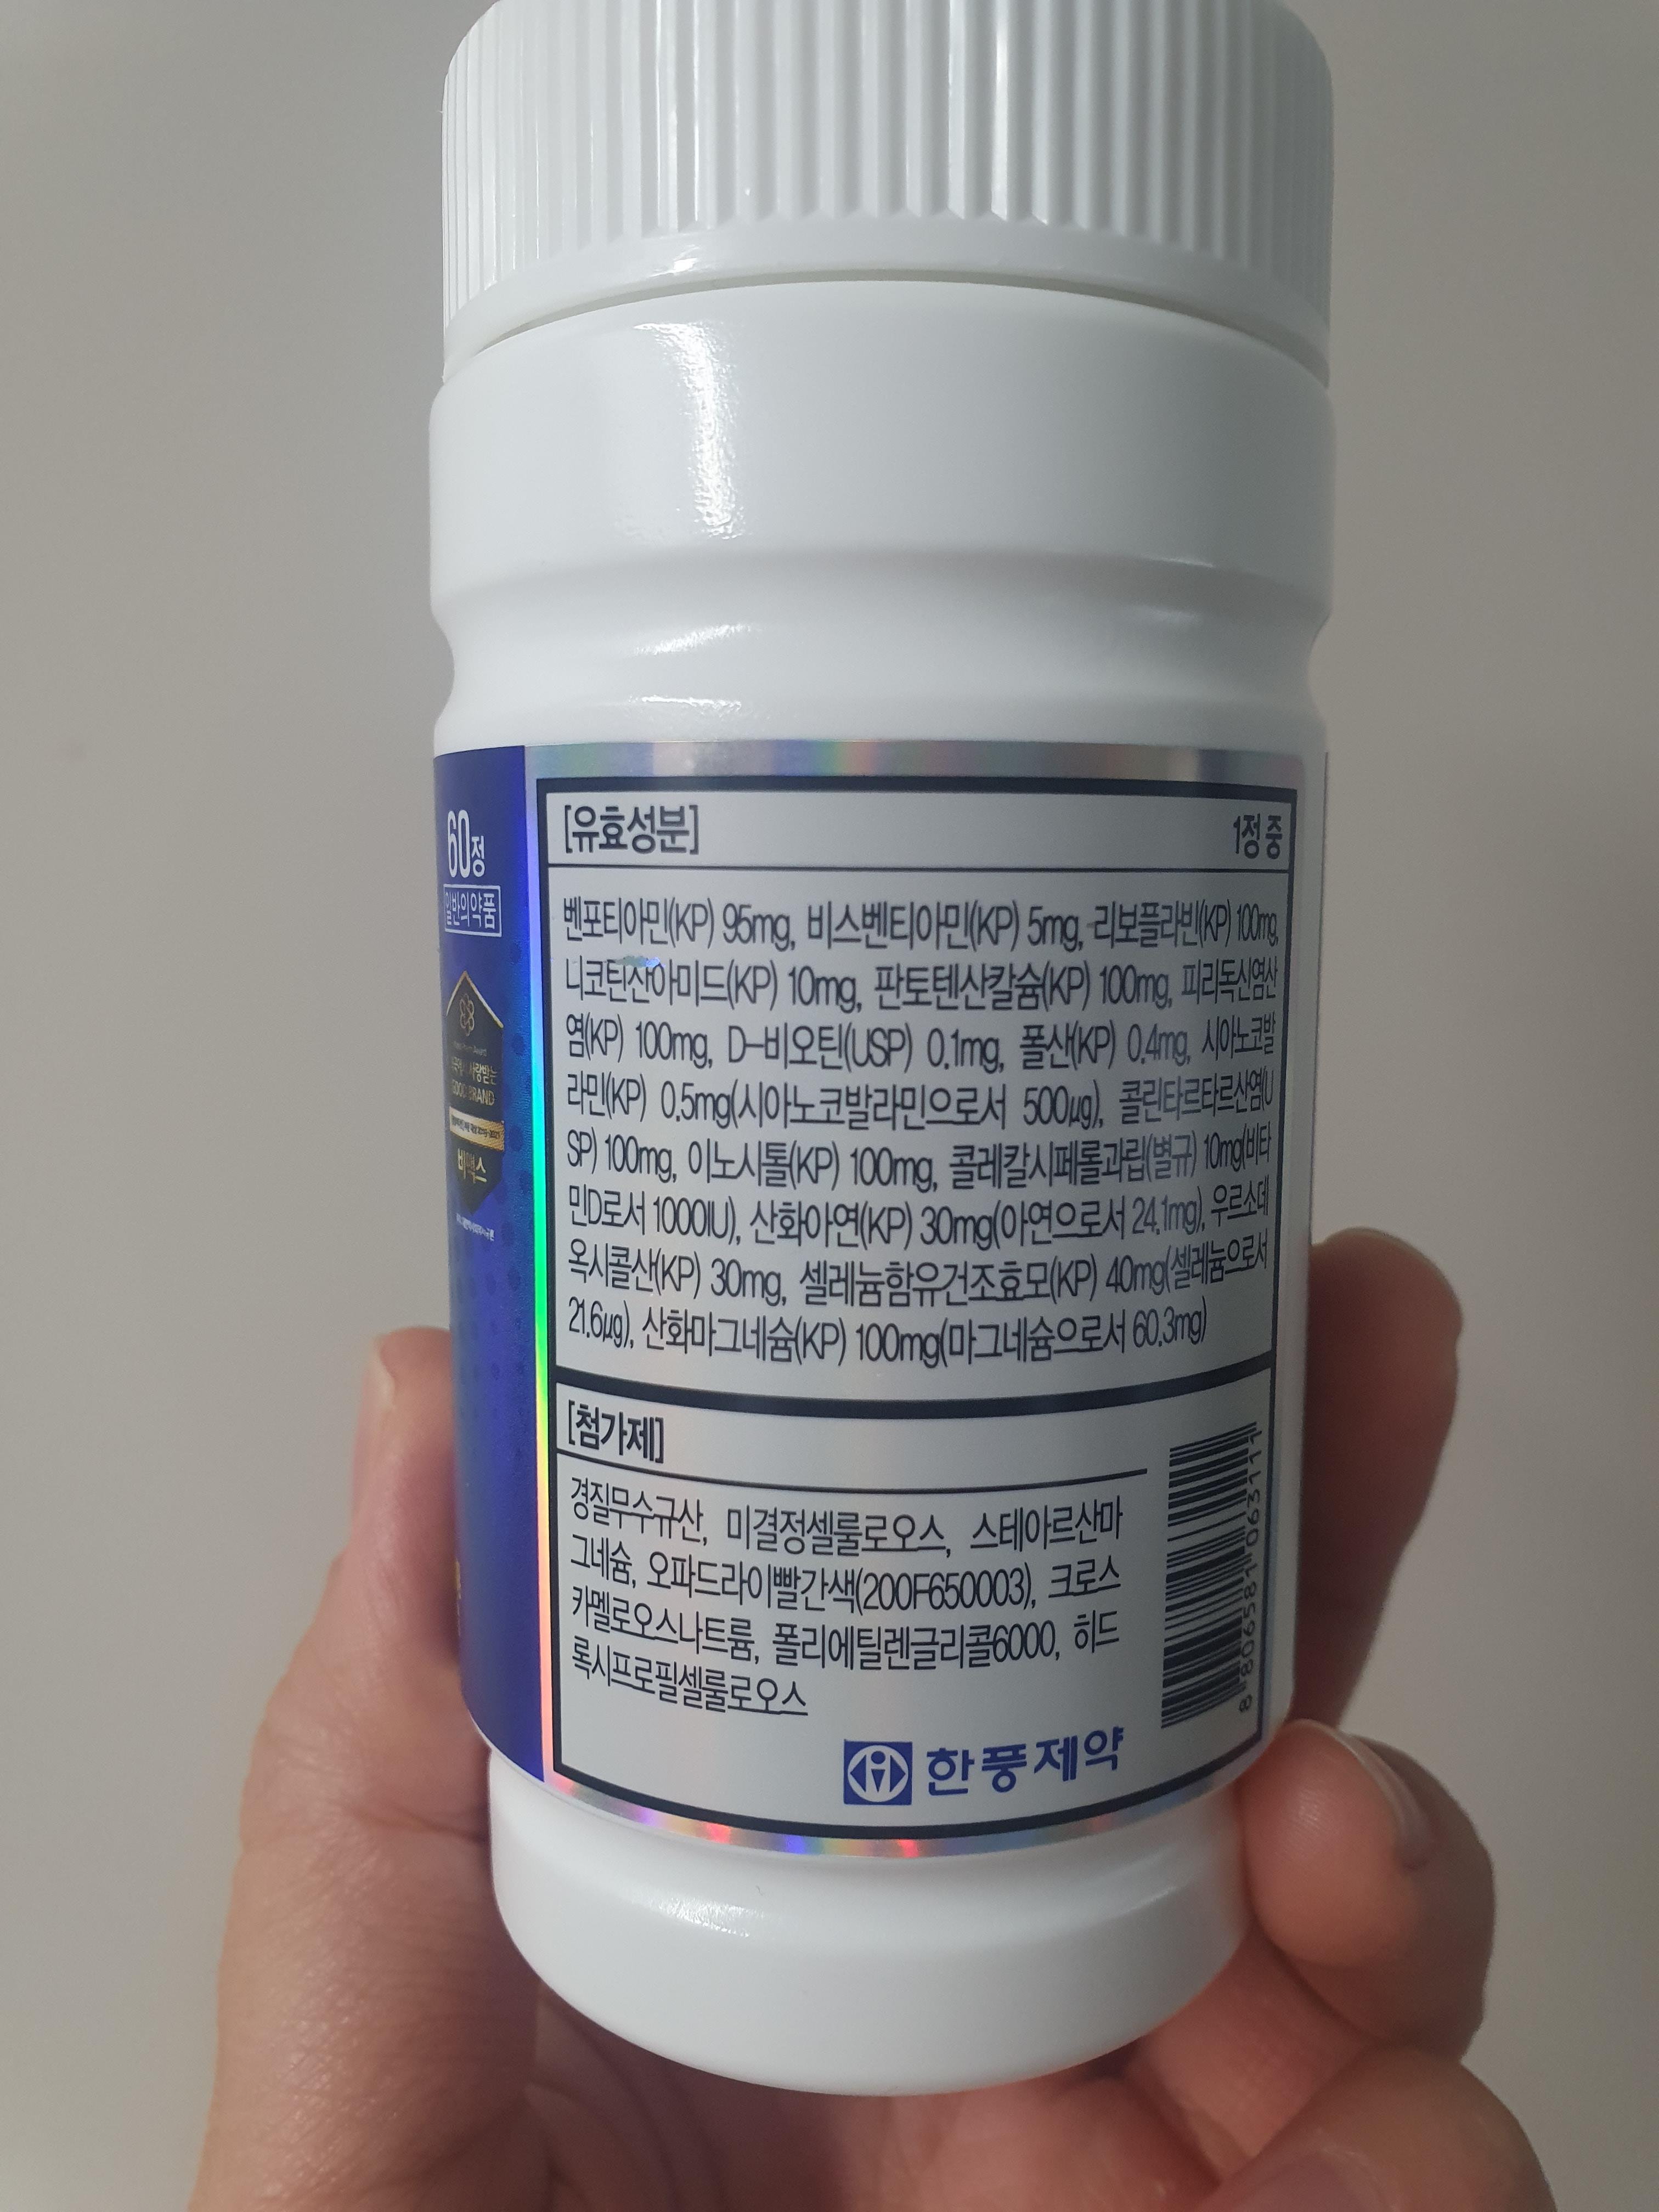

비타민b 영양제를 선택할 때는 비타민b 8종이 다 들어있는

제품으로 구매하는 것이 좋습니다.

비타민 b군 8종은 서로 흡수와 활성화를 돕기 때문에

함께 있어야 제대로 된 효능을 발휘할 수 있습니다.

특히, 빠른 효과를 위해서는 비타민b1 활성형이 들어있는 제품이

좋습니다.

비타민b 고함량 제품

요즘 인기있는 제품으로는 임팩타민 시리즈와 비맥스 시리즈가 있죠

저는 개인적으로 현재 비맥스 메타를 먹고 있습니다.

비맥스 시리즈 중에서도 가장 고함량이 비맥스 메타입니다.